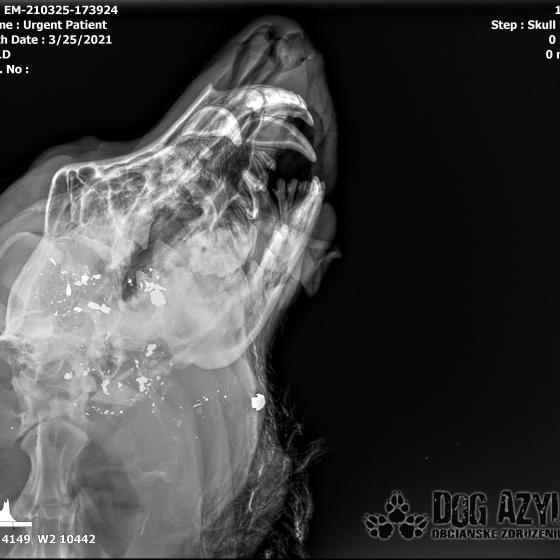

Strela zasiahla Barisa v oblasti lícnej kosti, ktorá mu rozdrvila sánku a následne putovala cez krk až po krčnú chrbticu. Úlomky z guľky (neviem ako sa to odborne volá) sa roztrieštili na "milión" kusov počas svojej cesty. Tieto úlomky sú všade (ako vidieť aj na RTG). Jeden (alebo niekoľko týchto úlomkov) sa dostali až po miechu, ale našťastie ju neprerazili. Toto spôsobilo, že Baris citlivosť v nohách na ľavej strane sice má, ale má poškodenú motoriku. Tieto úlomky sa z oblasti stavcov, miechy aj krku dnes odstránili, ale Barisko z ďaleka nemá vyhraté. Miecha je totiž zakrvácaná (opäť sa ospravedlňujem za nepresnosť a laickosť) a to, že ako veľmi je poškodená, alebo či jeho slabosť bola spôsobená "iba opuchom" sa ukáže cca do 24 hodín. Ak Baris nedajbože do zajtra stratí citlivosť v nohách, tak.. žiaľ... Ale! ak citlivosť zostane, prípadne nastane aj zlepšenie, tak vzplanie plamienok ďalšej nádeje a bojujeme ďalej!